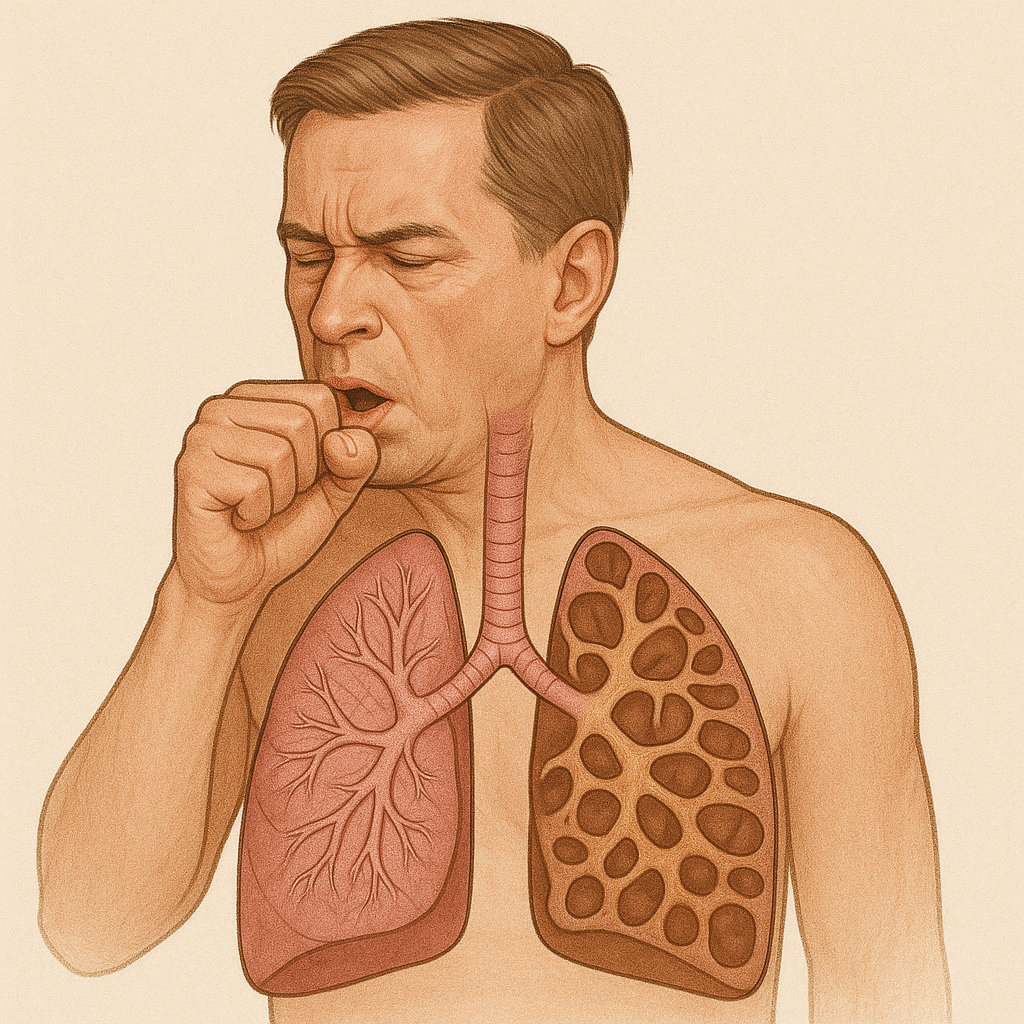

# Respiratory

Chronic Obstructive Pulmonary Disease (COPD)

क्रोनिक ऑब्स्ट्रक्टिव पल्मोनरी रोग (सीओपीडी)